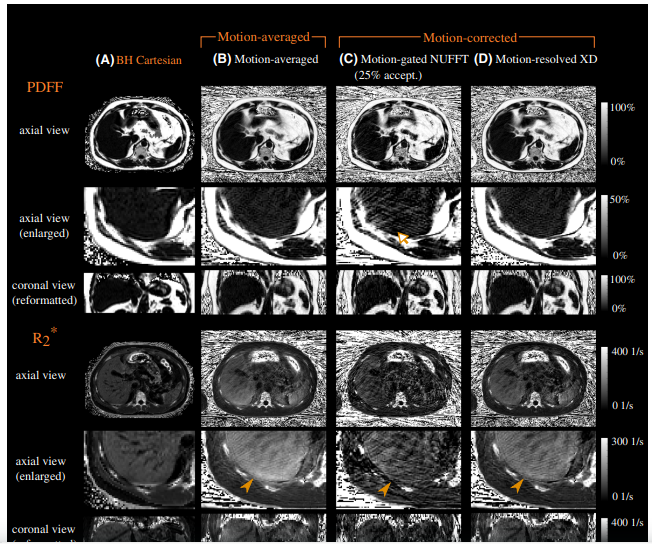

2. Free‐breathing fat and quantification in the liver using a stack‐of‐stars multi‐echo acquisition with respiratory‐resolved model‐based reconstruction.png

Schneider M, Benkert T, Solomon E, Nickel D, Fenchel M, Kiefer B, Maier A, Chandarana H, Block K

Magnetic Resonance in Medicine, 2020